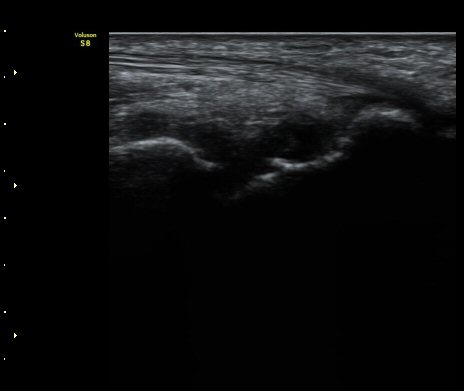

ÃÊÀ½ÆÄ °Ë»ç

¼Õ¸ñÀÇ Á¾´Ü

ÁÖ»ó°ñ ¼±»ó°ñÀýÀº ´Ü¼ø¹æ»ç¼± ÃÔ¿µ ½Ã È®ÀεÇÁö ¾ÊÀº °æ¿ì°¡ ¸¹Àºµ¥ ÀÌ ¶§ ÃÊÀ½ÆÄ

°Ë»ç°¡ ÁÖ»ó°ñ °ñÀý Áø´Ü¿¡ ¸Å¿ì À¯¿ëÇÏ´Ù. ±×·¯¹Ç·Î ¼Õ¸ñ ´ÙÄ£ ÈÄ Áö¼ÓÀûÀÎ ÅëÁõÀ»

È£¼ÒÇϰí ÁÖ»ó°ñ ºÎÀ§ ¾ÐÅëÀ» º¸ÀÌ´Â °æ¿ì ÃÊÀ½ÆÄ°Ë»ç¸¦ ½ÃÇàÇÏ¿© ÁÖ»ó°ñ °ñÀý ¿©ºÎ¸¦

È®ÀÎÇØ¾ß ÇÑ´Ù.

ÃÊÀ½ÆÄ°Ë»ç¸¦ ½ÃÇàÇÒ ¼ö ¾ø´Â °æ¿ì´Â ÄÄÇ»ÅÍ ÃÔ¿µ°Ë»ç¸¦ ÁÖ»ó°ñ °ñÀýÀ» È®ÁøÇÒ ¼ö ÀÖ´Ù.